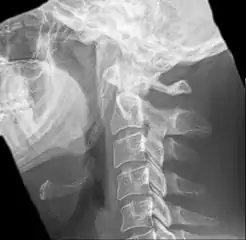

Radiograph, lateral view showing elongated stylohyoid process and stylohyoid ligament ossification

Radiograph, lateral view showing joint-like formation in ossified stylohyoid ligament